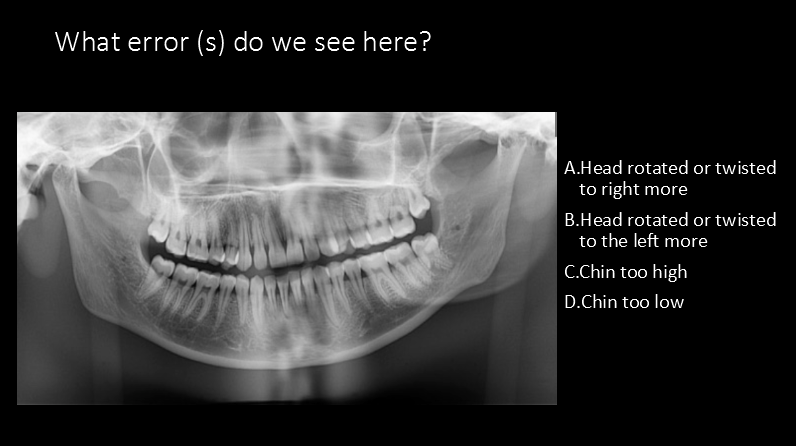

What errors do we see?

A. Chin too high and forward

B. Pt. is laughing

C. Chin too low and head too far back

D. Chin too low and head is too far forward